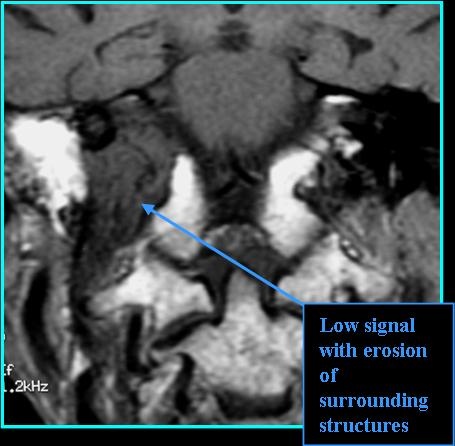

- Look for bony erosion on CT and "salt and pepper" appearance on T1 and T2 MR (Moore et al. 2016)

- On CT: look for permeative-destuctive bone changes, especially jugular spine erosion on non-contrast; intense enhancement with contrast

- On MR: "salt" appearance on T1 (white dots), "pepper" appearance on T2 (black dots), hyperintense and good spread definition on post-contrast T1